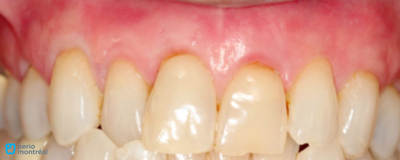

Pre-Op and Post-Op Pictures

- PRE-OP

- POST-OP

Final result

The final results after 2 years show the root coverage obtained and the stability of gingival tissues over time. Post-operative recession ranged from 0 mm to 1 mm. The patient was satisfied with the aesthetics and did not want new Class Vs.